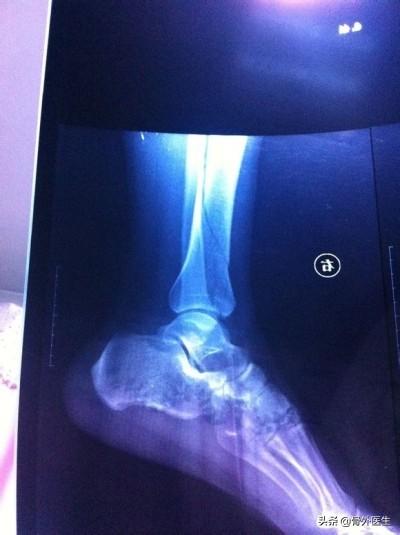

微创经皮钢板内固定结合弹性髓内钉治疗成人胫腓骨远端骨折

Minimally Invasive Percutaneous Plate Osteosynthesis And Elastic Nail System In The Treatment Of Distal Tibiofibular Fracture In Adults